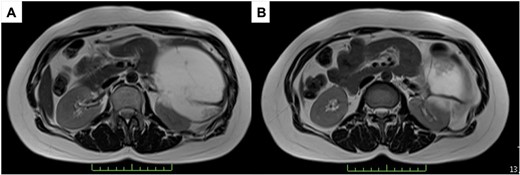

A 43-year-old woman visited our hospital because of abdominal pain. Her medical history was unremarkable and not suggestive of acute pancreatitis or cholelithiasis. Laboratory studies revealed slight anemia and normal levels of amylase and inflammatory markers. Contrast-enhanced computed tomography (CT) showed a multilocular cystic lesion with a septum and a small, hyperdense area suggestive of intratumoral bleeding (Fig. 1). Magnetic resonance imaging (MRI) revealed a multilocular cystic lesion with a thick septum on T2-weighted imaging (Fig. 2). Those findings suggested a pancreatic cystic tumor, including the possibility of MCN, and we decided to perform distal pancreatectomy with splenectomy. A midline incision was made in the upper abdomen. A 15-cm tumor was identified in the tail of the pancreas, displacing the stomach and body of the pancreas. We mobilized the tumor in the tail of the pancreas along with the pancreatic body and spleen en bloc from the retroperitoneum. The tumor was extirpated by dissecting the body of the pancreas (Fig. 3).

T2-weighted MRI; (A) the tumor has a thick fibrous capsule; (B) the tumor has a thick fibrous septum.